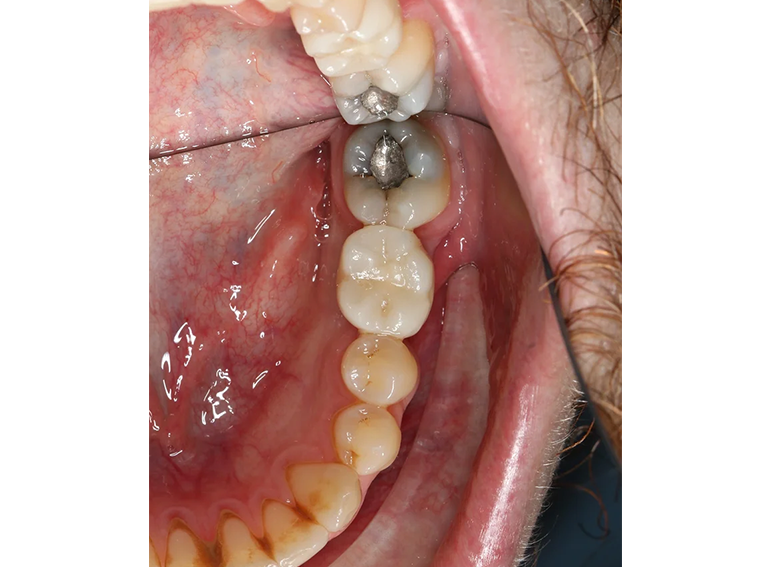

Implant to replace a molar with external cervical resorption.